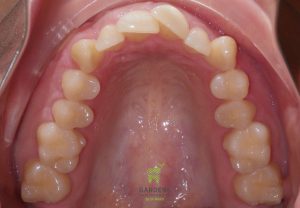

Initial and Final photos correcting crowded maxillary arch for an adult patient